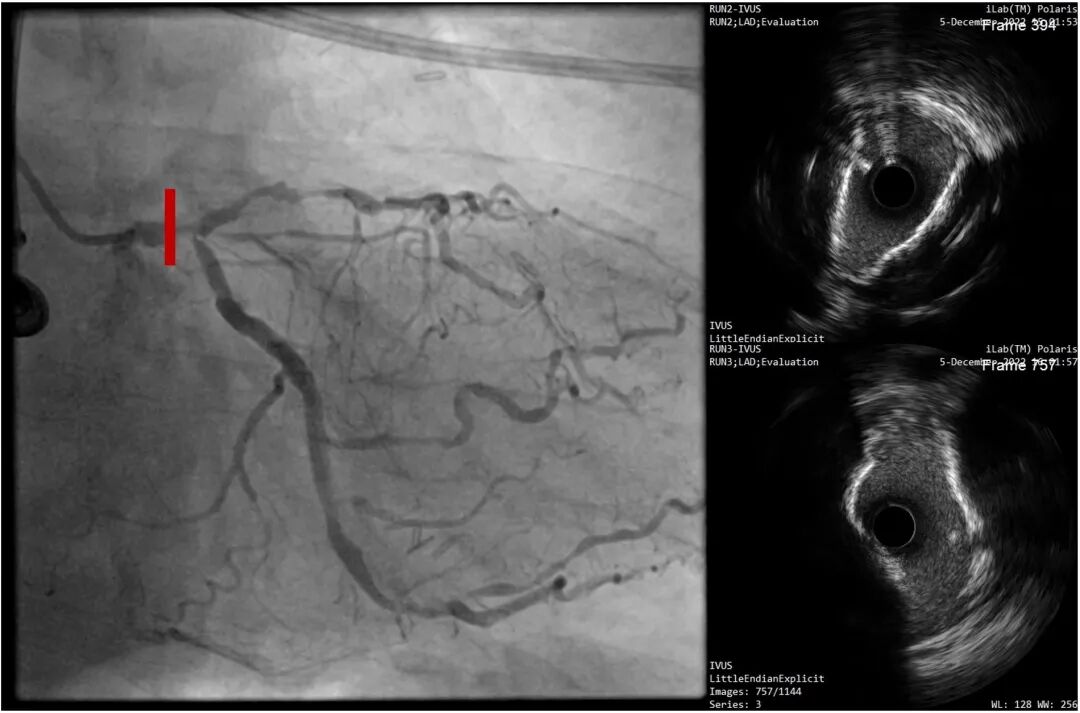

LAD近段-LM IVUS提示为270°环形钙化

复查LAD近段-LM IVUS,钙化环明显断裂

对LAD近段-LM 进行IVUS检查,提示重度钙化病变

LAD开口前后IVUS

LM前后IVUS

LCX开口前后IVUS